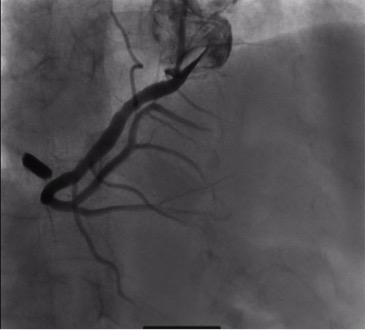

Dị

vật hình hạt thóc trên phim chụp mạch vành

Khi siêu âm tim ghi nhận người bệnh bị hở van 3 lá rất nặng, tim

phải dãn lớn, có chỉ định phẫu thuật sửa van 3 lá. Tuy nhiên, khi xem phim XQ

ngực thẳng và chụp mạch vành, các bác sĩ phát hiện trong tim có một mảnh dị vật

cản quang. Sau khi hội chẩn, các bác sĩ quyết định chụp MSCT không cản quang

cho người bệnh để xác định vị trí của dị vật. Sau khi phân tích kết quả chụp,

kết luận được dị vật nằm trong nhĩ phải. Sau khi hội chẩn và bàn bạc cùng gia

đình và người bệnh, TS BS. Nguyễn Hoàng Định – Trưởng khoa Phẫu thuật tim mạch

quyết định vẫn sẽ phẫu thuật nội soi tim để sửa van 3 lá và lấy dị vật.

được tìm thấy ghim trong nhĩ phải, nằm sát đường đi của động mạch vành phải. TS

BS. Nguyễn Hoàng Định chia sẻ: “Người bệnh đã rất may mắn, vì chỉ cần lệch vài

mm, mảnh dị vật sẽ làm tổn thương động mạch vành phải, và tính mạng của người

bệnh khi đó sẽ khó lòng mà giữ được”.